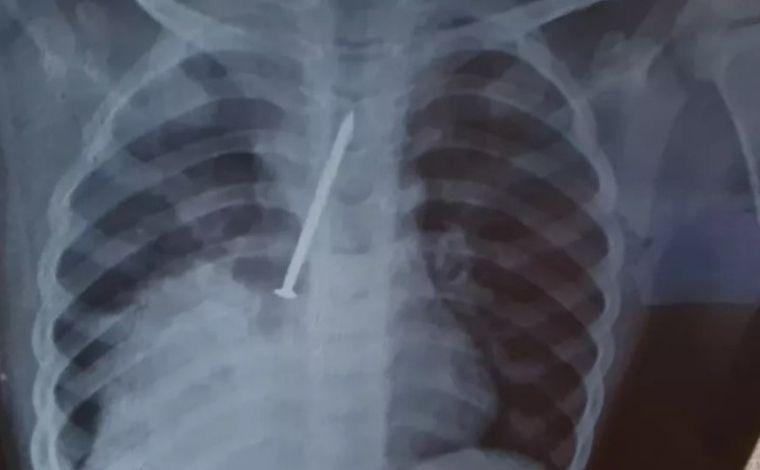

Os sintomas de Cauan pioraram e os pais decidiram pagar por um exame de raio-X particular, que constatou o prego no pulmão. O garoto foi transferido para o Hospital Geral do Estado (HGE), onde passou por uma cirurgia.

Como o objeto havia perfurado o pulmão, o menino teve de ficar internado na Unidade de Terapia Intensiva (UTI), onde morreu dois dias depois.